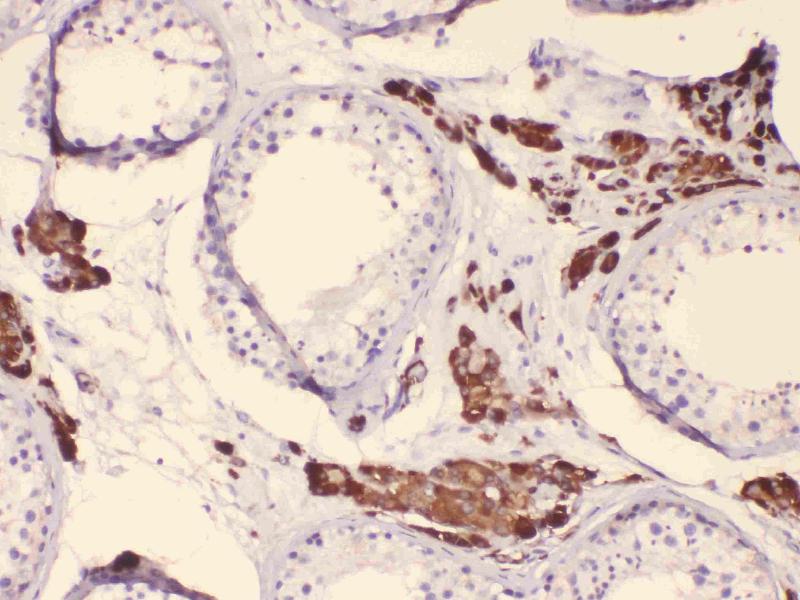

CYP17A1 Reactivité: Souris, Rat WB, ELISA, IHC (p) Hôte: Lapin Polyclonal unconjugated

Pubmed 3 références

N° du produit ABIN720071

357,70 €

Plus frais de livraison 40,00 € et TVA

100 μL

Destination: France

Envoi sous 8 à 12 jours ouvrables